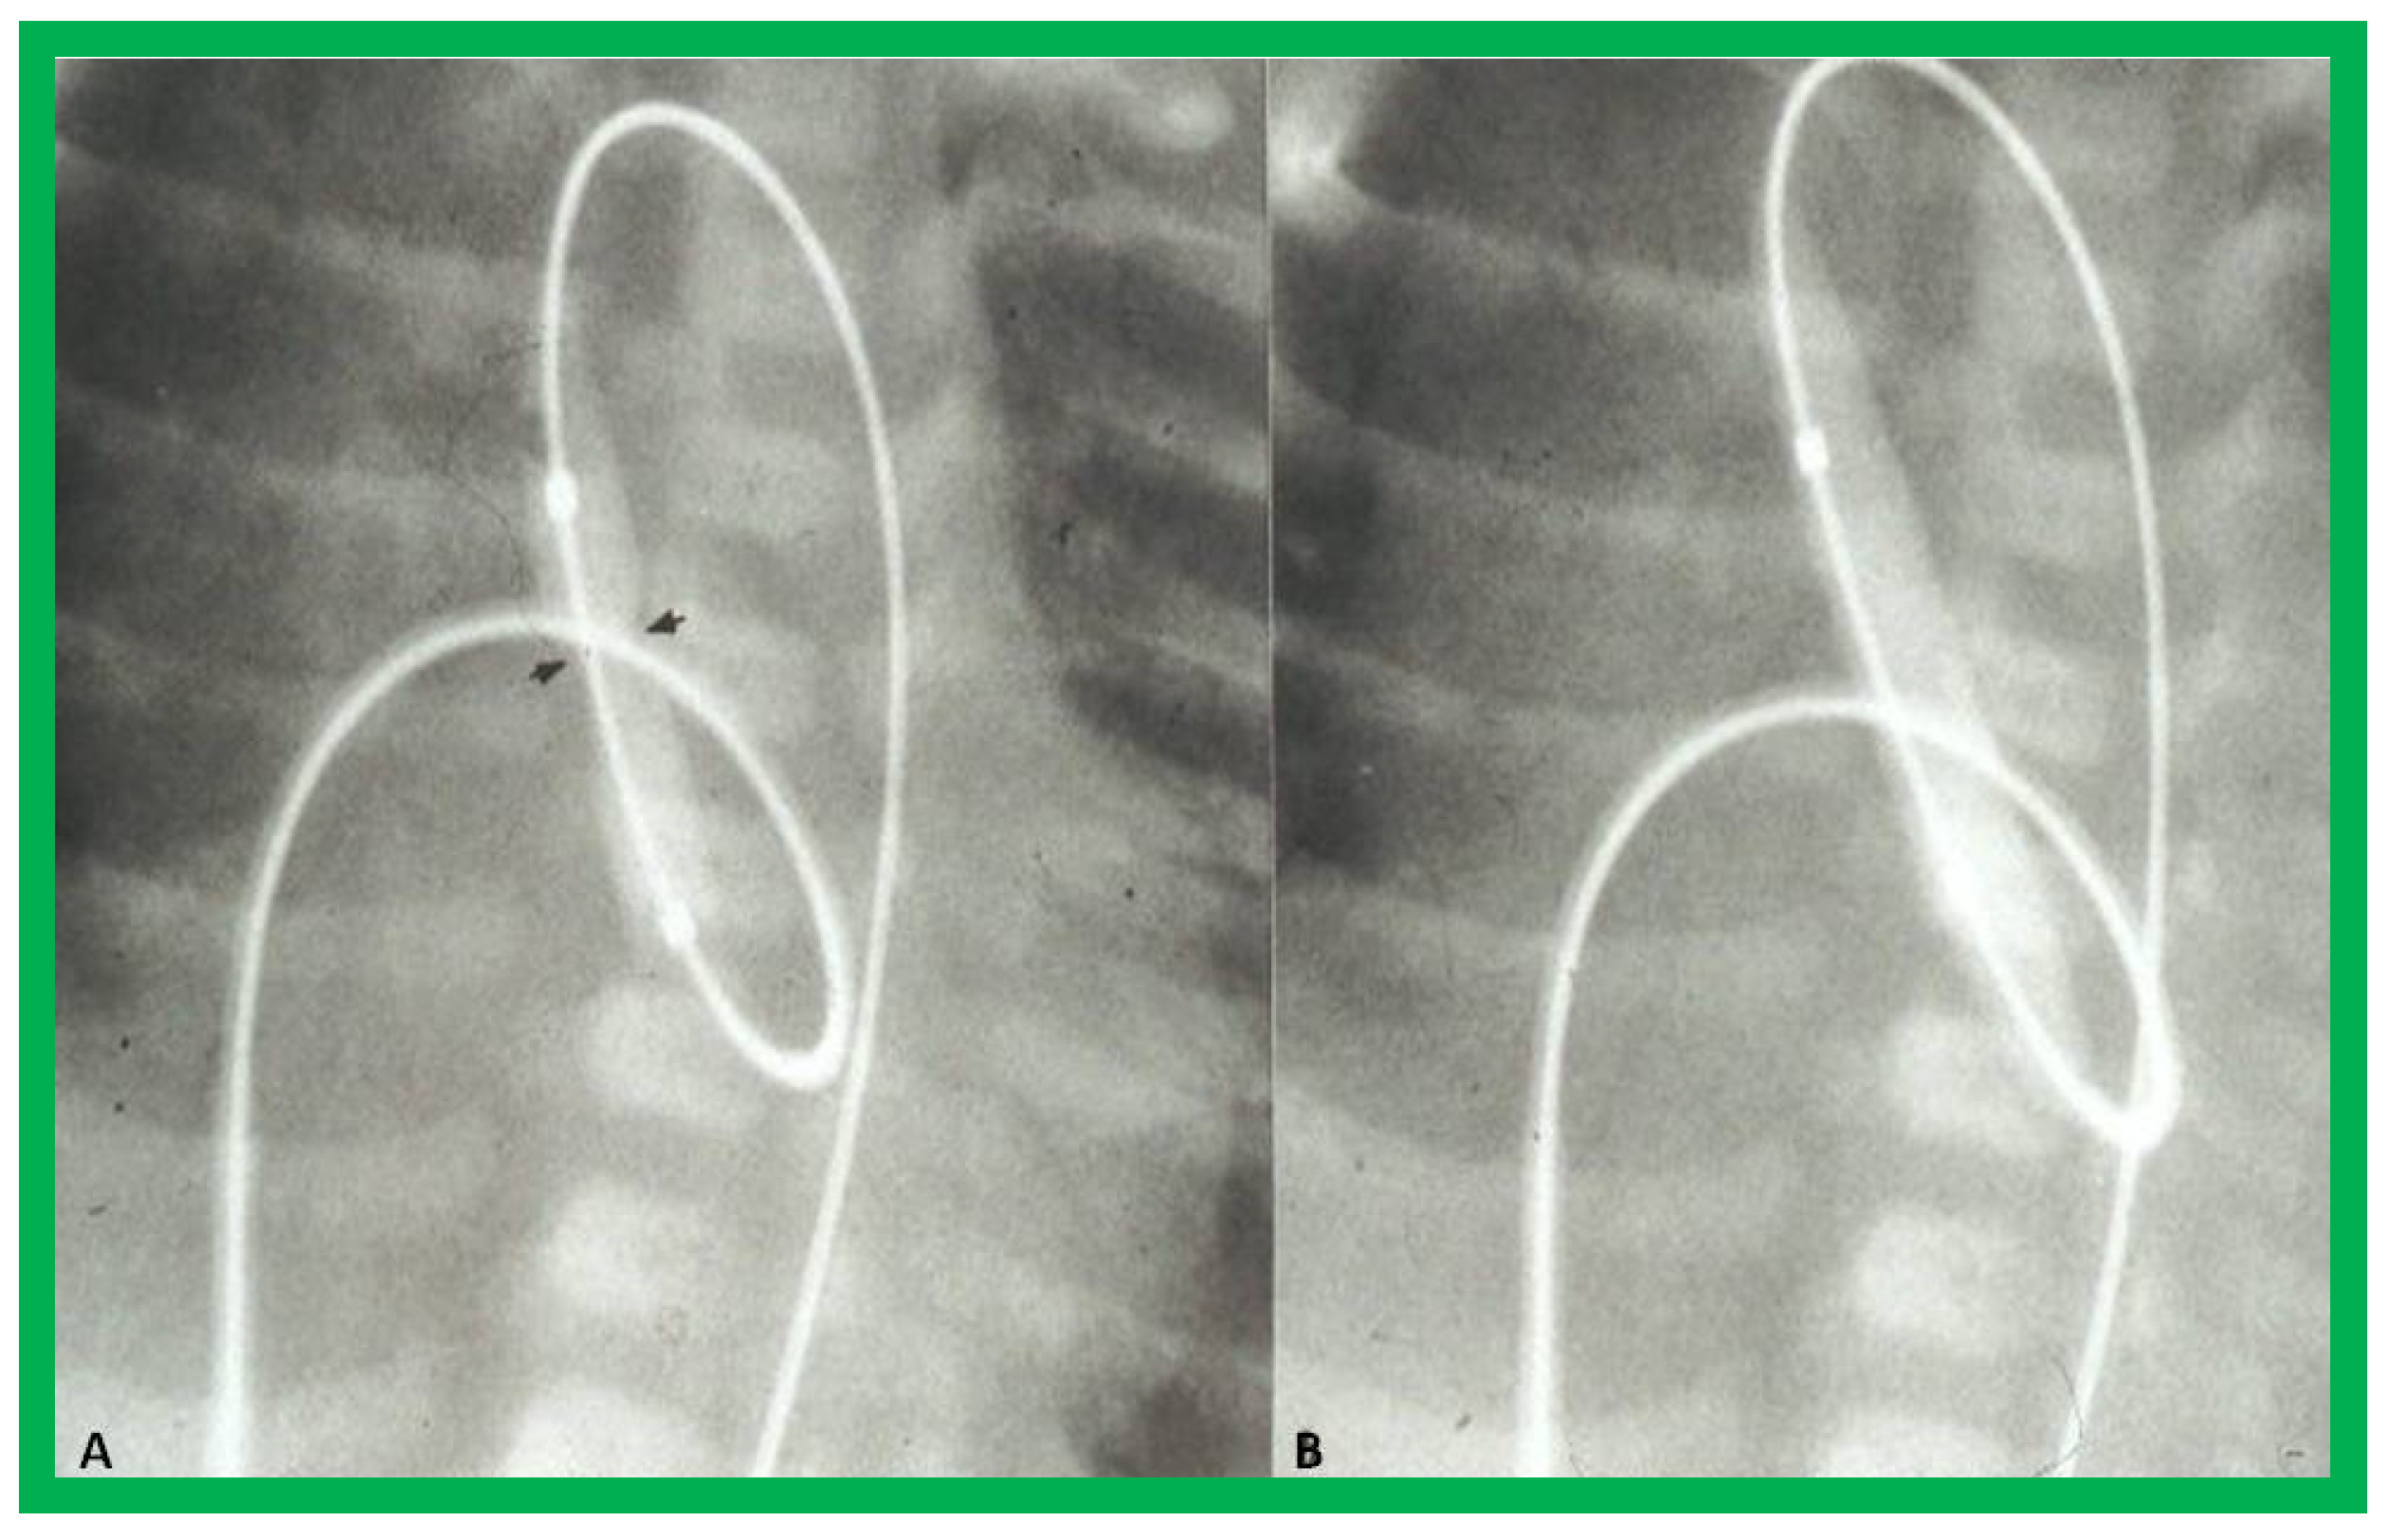

- Rao, P.S.; Jureidini, S.B. Transumbilical venous anterograde, snare-assisted balloon aortic valvuloplasty in a neonate with critical aortic stenosis. Catheter. Cardiovasc. Diagn. 1998, 45, 144–148. [Google Scholar] [CrossRef]

- Rao, P.S. Anterograde balloon aortic valvuloplasty in the neonate via the umbilical vein. Card. Cardiovasc. Interv. 2003, 59, 291–292. [Google Scholar] [CrossRef] [PubMed]

- Rao, P.S. Role of interventional cardiology in neonates: Part II-Balloon angioplasty/valvuloplasty. Neonatol. Today 2007, 2, 1–12. [Google Scholar]

- Rao, P.S. Anterograde transumbilical venous balloon aortic valvuloplasty. Card. Cardiovasc. Interv. 2002, 56, 439. [Google Scholar] [CrossRef] [PubMed]